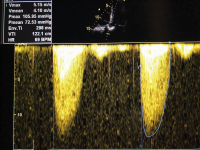

CW-Doppler - Overgain

Abbildung 3: CW-Doppler: Aortenklappenstenose vor hellem Hintergrund = „Overgain“.

Abbildung 4: CW-Doppler: Aortenklappenstenose. Es handelt sich um den gleichen Patienten wie bei Abb. 3, aber jetzt bei dunklem Hintergrund; ohne „Overgain” viel geringere VTI.

Keywords: CW-DopplerKardiologieOvergain